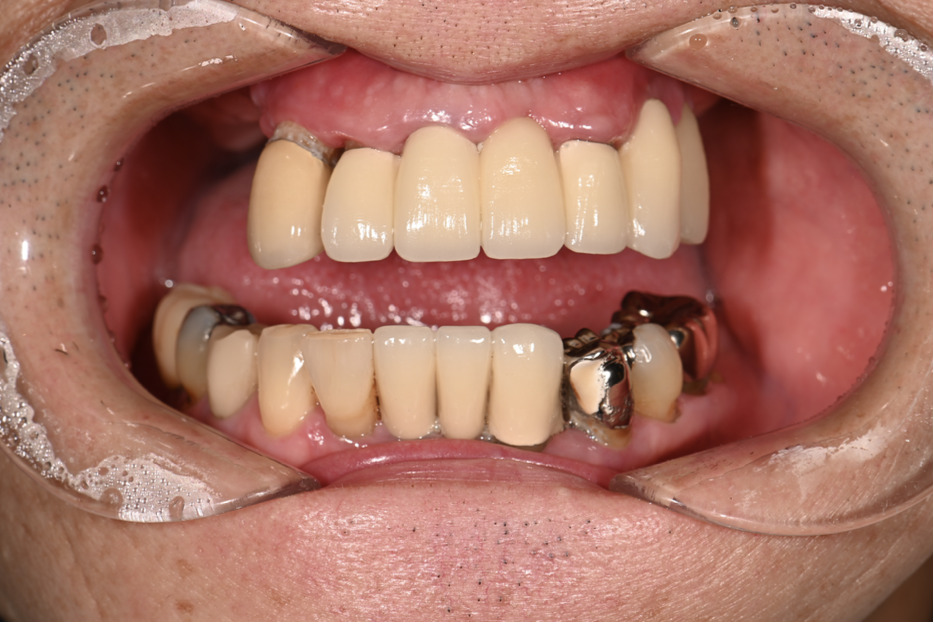

| 主訴 | 全体的にきれいにしたい |

|---|---|

| 治療内容 | 午前中に上下顎共に重度の歯周病、虫歯のため全ての歯を抜歯させていただき下顎はインプラントの土台を3本埋入し歯型を取り午後に上部構造(下顎全ての歯)を装着、上顎は一度総入れ歯を装着させていただきました。 治療が1日で完了しその日のうちに噛めるようになります。 |

| 治療期間 | 2回(1回目に資料取りをさせていただき2回目に下記の全ての治療をさせていただきました。) |

| 治療費 | 250万円 |

| 治療 リスク | 抜歯した部位などに関しては当日痛みが出ますので痛み止めなどを処方させていただきます |